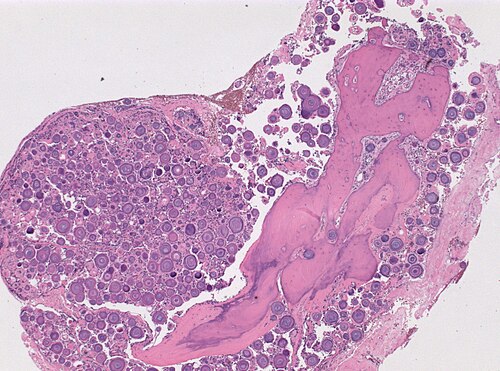

Exision of dura-based, calcified tumor.

Intermediate magnification

Intermediate magnification. H&E stain.

These round, calcified structures look like Psammoma bodies.

Psammomatous meningioma, WHO grade I

Comment: It is said, that psammoma bodies represent a process of dystrophic calcification or as an active biologic barrier to tumor spread ultimately leading to degeneration/death of tumor cells. [1] [2]